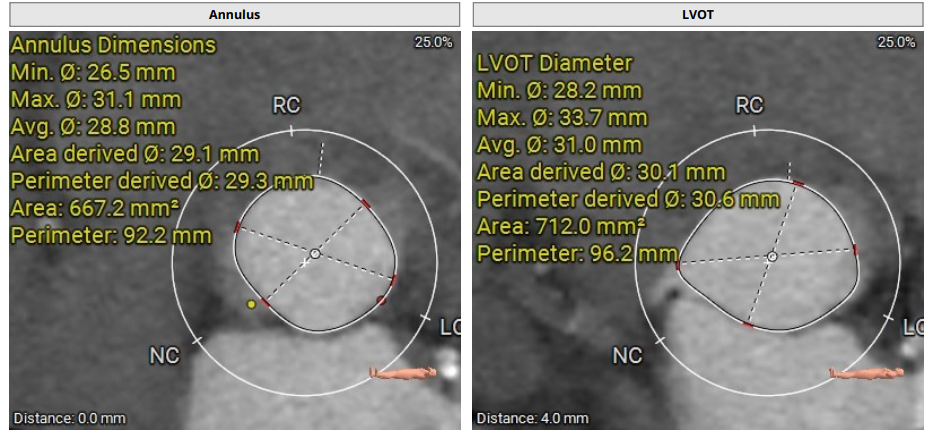

术前评估

术前影像评估提示,患者为典型三叶瓣结构,瓣窦分布均匀,无明显钙化,主动脉瓣环直径29.3mm,左室流出道直径30.6mm,STJ直径37.8mm,升主动脉直径40.5mm,双侧冠脉开口高度充足(左冠17.0mm,右冠27.6mm),无冠脉阻塞风险,左室-主动脉夹角137°,存在一定同轴性挑战。

CTA评估(上下滑动查看更多照片)

瓣膜选型:JS/TAVI-31瓣膜